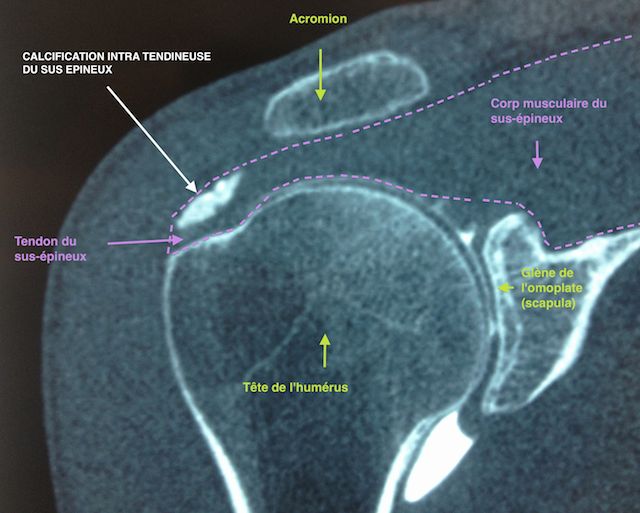

Puis, il pourra être utile de faire une IRM ou un arthroscanner, pour localiser la calcification et évaluer sa taille par rapport à l’épaisseur du tendon.

Calcification intra-tendineuse vue de face à l'arthroscanner

Figure 3 : Calcification intra-tendineuse vue de face à l'arthroscanner

Les calcifications sont situées dans le tendon du sus-épineux dans 80 % des cas. Dans 15 % des cas, elles se situent au niveau du tendon infra-épineux et dans 5 % des cas, au niveau du tendon sous-scapulaire.

On définit 3 types de calcifications :

• Calcifications type A : denses, homogènes, à contours nets.

• Calcifications type B : denses, homogènes, multilobées à contours nets.

• Calcifications type C : inhomogènes, à contours flous disséminée dans le tendon.